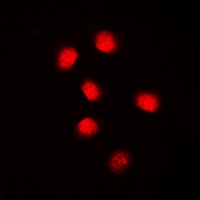

Immunofluorescent analysis of Cyclin E1 staining in MCF7 cells. Formalin-fixed cells were permeabilized with 0.1% Triton X-100 in TBS for 5-10 minutes and blocked with 3% BSA-PBS for 30 minutes at room temperature. Cells were probed with the primary antibody in 3% BSA-PBS and incubated overnight at 4 °C in a humidified chamber. Cells were washed with PBST and incubated with a DyLight 594-conjugated secondary antibody (red) in PBS at room temperature in the dark.